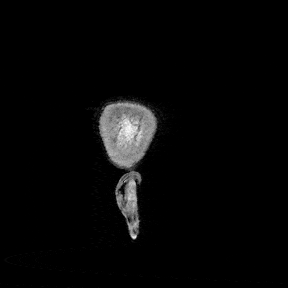

Turning anatomy into 3D models

Eventually I started thinking about turning this information into a 3D model. Unfortunately, FreeSurfer doesn’t provide 3D meshes out of the box. I had only:

- Cortical surface files: a map of the pial surface of the brain

- Surface annotations: annotations for the aforementioned cortical map, associating regions with names

- Volumetric segmentations: descriptions of which voxels in the 3D structure of my brain corresponded to which parts

To extract the models, I used the volumetric segmentations, essentially demarcations of where exactly each region was. The strategy was:

- Isolate one label as a binary mask

- Crop to its bounding box

- Run a marching cubes algorithm to create a 3D surface that would fit the label boundaries

This created quite clean 3D models that could be used with Three.js, 3D printing software or any model viewer. The remaining work was mostly pragmatic - I had to reduce the size of the model to ensure it would load quickly on the website. This involved decimation to reduce face count and smoothing to remove faceting (essentially 3D pixelation).